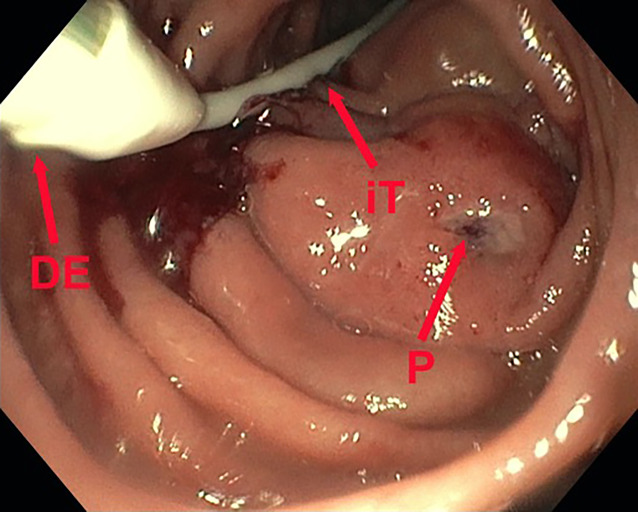

[Presentation of a new pre-emptive endoscopic treatment concept in duodenal interventions exemplified by an iatrogenic duodenal perforation after percutaneous transrenal nephrostomy. German version].